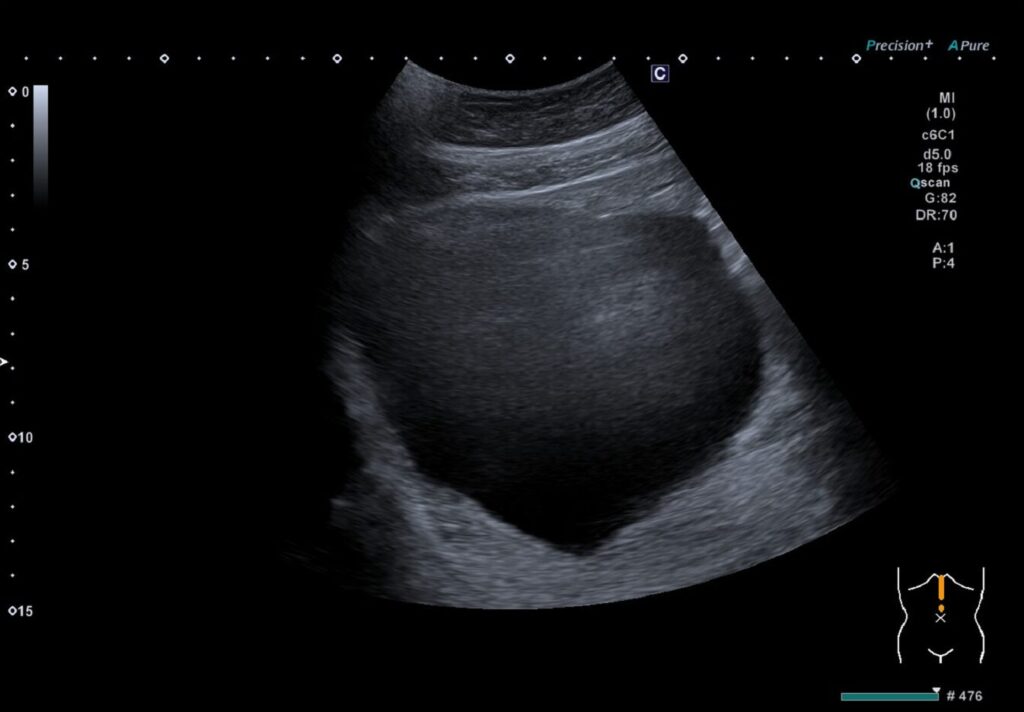

① サイズが10cm以上の嚢胞

実際のサイズ感をみるとこんな感じです。

画面全体が嚢胞に(笑)

ちなみにこの症例では痛み等はなかったので経過観察です。

過去には巨大嚢胞で外科的手術になった症例に数件出会ったこともあります。